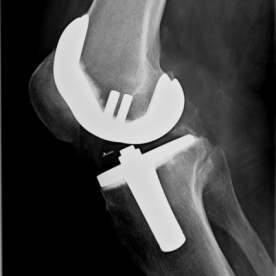

Bei einer Arthrose handelt es sich um eine Knorpelabnutzung in einem Gelenk, wobei unterschiedliche Ausprägungsgrade möglich sind. Je nach Ausprägungsart kommen konservative (Entzündungshemmende Medikamente, physikalische Therapie, orthopädische Hilfen) oder operative Verfahren (arthroskopische Spülung bzw. Gelenktoilette, Knochenumstellungen, Knorpelknochenzelltransplantationen oder prothetische Versorgung) in Frage.

Röntgenbilder